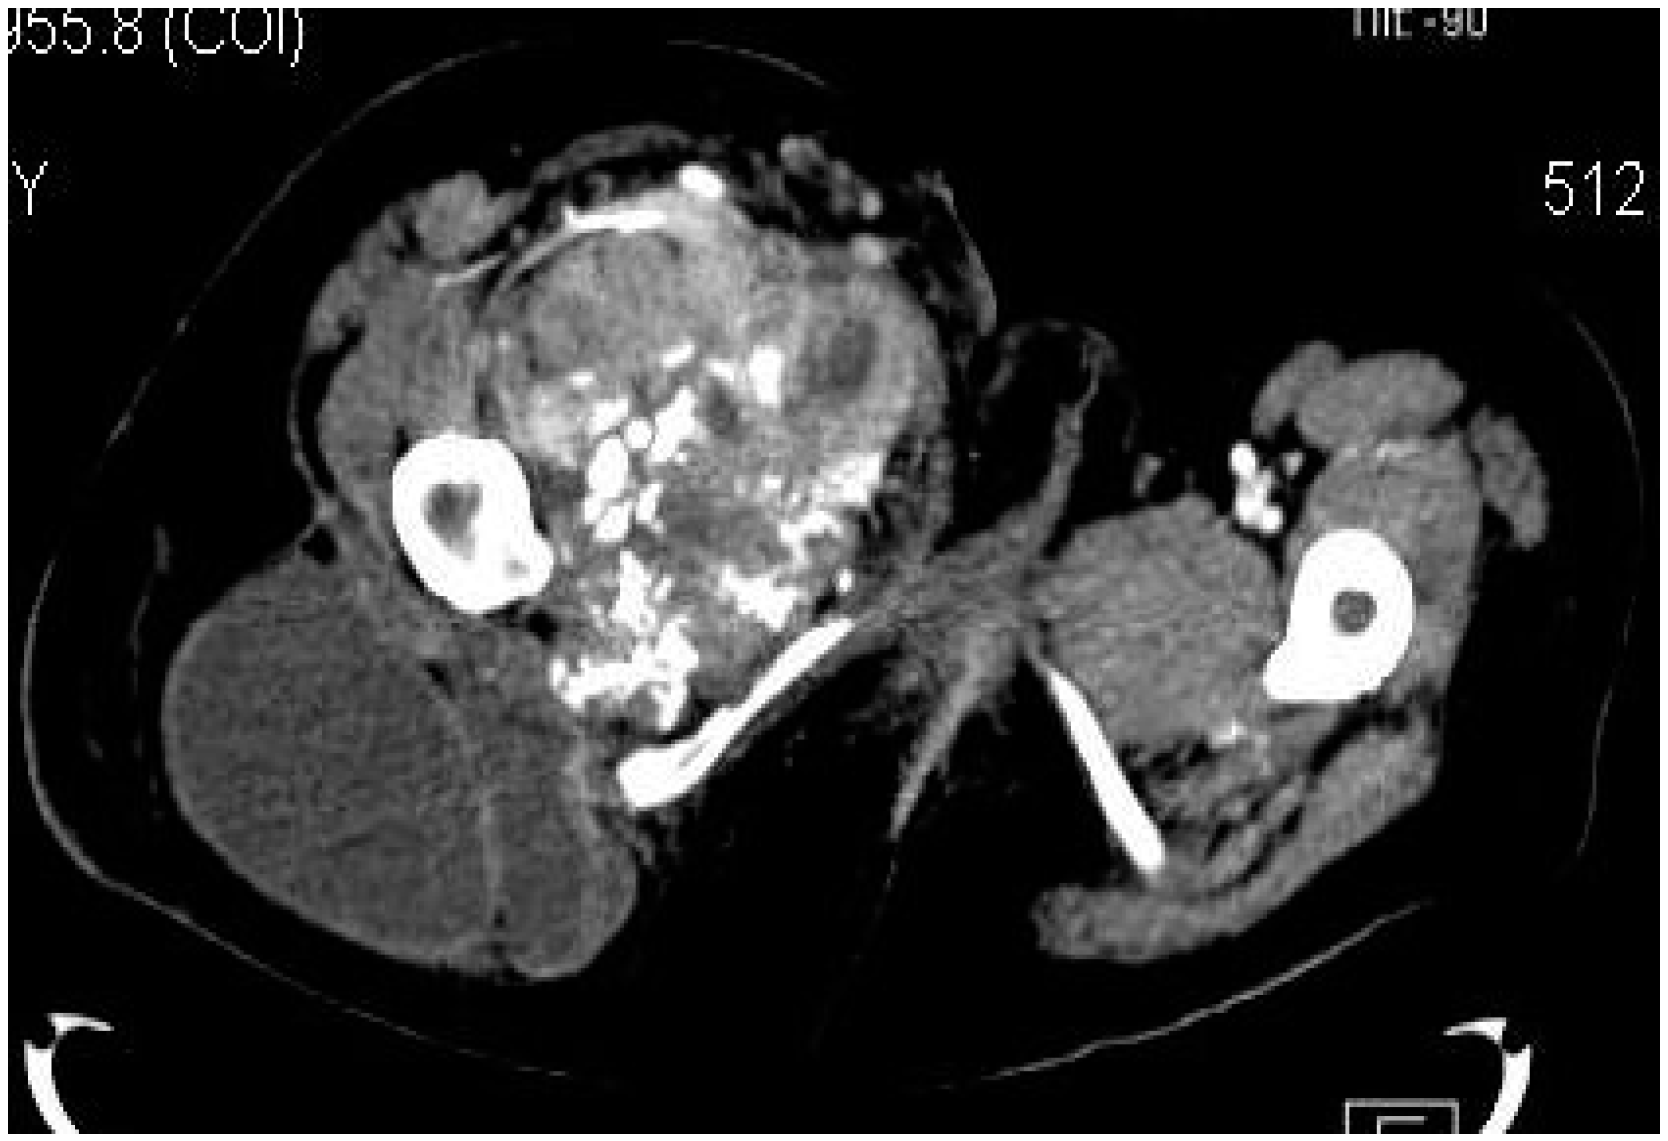

Computed tomography (CT) is usually performed either if the MRI is contraindicated (e.g., due to the presence of orthopedic implants), is unavailable or if the radiologists need additional information regarding the local bone involvement or better visualization of the intratumoral calcifications (Figure 4, Figure 5 and Figure 6).

Figure 4.

Axial CT-scan: evident enlargement of the right thigh; heterogeneous soft-tissue mass with calcifications, adjacent fat infiltration and skin thickening—synovial sarcoma, M, 26 YO patient.